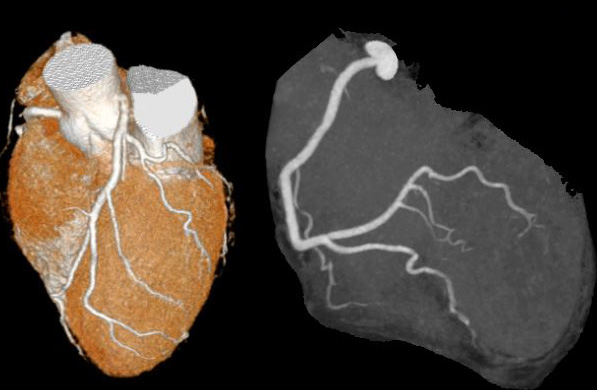

図15. 320列多列検出器型CTによる造影冠動脈CT像.1秒以下の撮影で心臓全体を撮影できる.

さらに1990年代後半に,多列検出器型CT(multi-detector row CT, MDCT)が登場した.従来,X線検出器はガントリー内面に弧状に1列に配置されていたが,これを複数列にすることにより,同時に複数枚の断面を撮影でき,撮影時間もそれに応じて短縮する( 図14)*.1998年のRSNAで,GE社,Siemens社が,翌年に東芝社が4列MDCTを発表し,その後各社が競って8列,16列,32列,64列と検出器数を増加させた.またMDCTをヘリカル技術と組み合わせることにより,広範囲にわたる等方向性のボリュームデータを短時間に得ることができるようになった.さらに2007年,東芝は320列装置によりヘリカル撮影を行うことなく1回転,1秒以下で16cm幅の撮影が可能な面検出器型CT(area detector CT, ADCT)を開発し,これにより心臓の動態CTは大きく進歩した(図15).